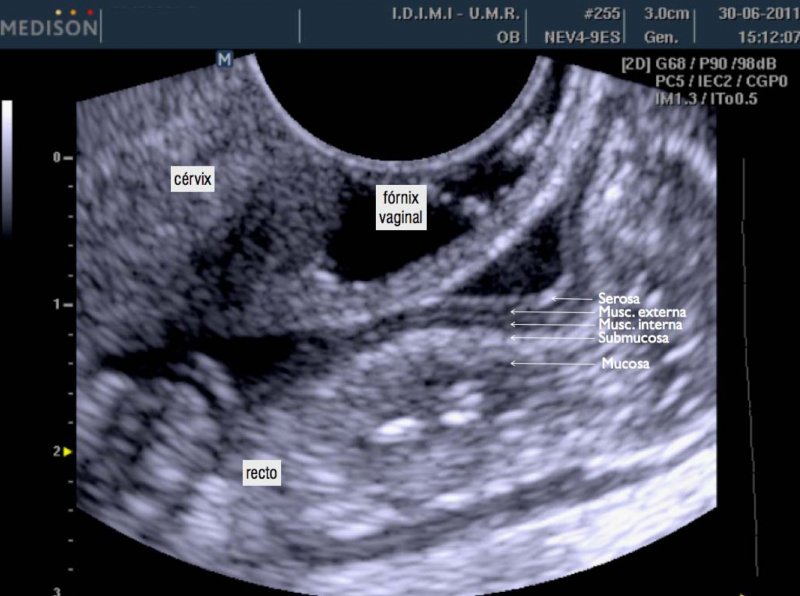

ultrasonido pelvico salud digna El precio del ultrasonido pélvico en salud digna laboratorios puede variar ya que hay varios tipos de ultrasonido que componen la zona pélvica. Ultrasonido de abdomen con un costo de $105. Las imágenes ecográficas del ultrasonido pélvico pueden también ayudar a determinar posibles quistes ováricos o fibromas uterinos, así como cáncer ovárico o uterino. Un ultrasonido o ecografía es un procedimiento seguro que utiliza ondas de sonido no audibles para el ser humano, las cuales escanean diferentes partes del cuerpo, con el propósito de crear una imagen del interior. El ultrasonido pélvico es primordial para diagnosticar el origen del dolor pélvico, sangrado anormal, u otros problemas menstruales. En un ultrasonido obstétrico, se explora tu abdomen y cavidad pélvica durante el embarazo, con lo que es posible. Un ultrasonido intravaginal también puede ayudar a diagnosticar problemas de fertilidad en la vejiga, los riñones y la cavidad pélvica. Ultrasonido 4d con un costo de $230.

Ultrasonido pelvico

Source: es.slideshare.net